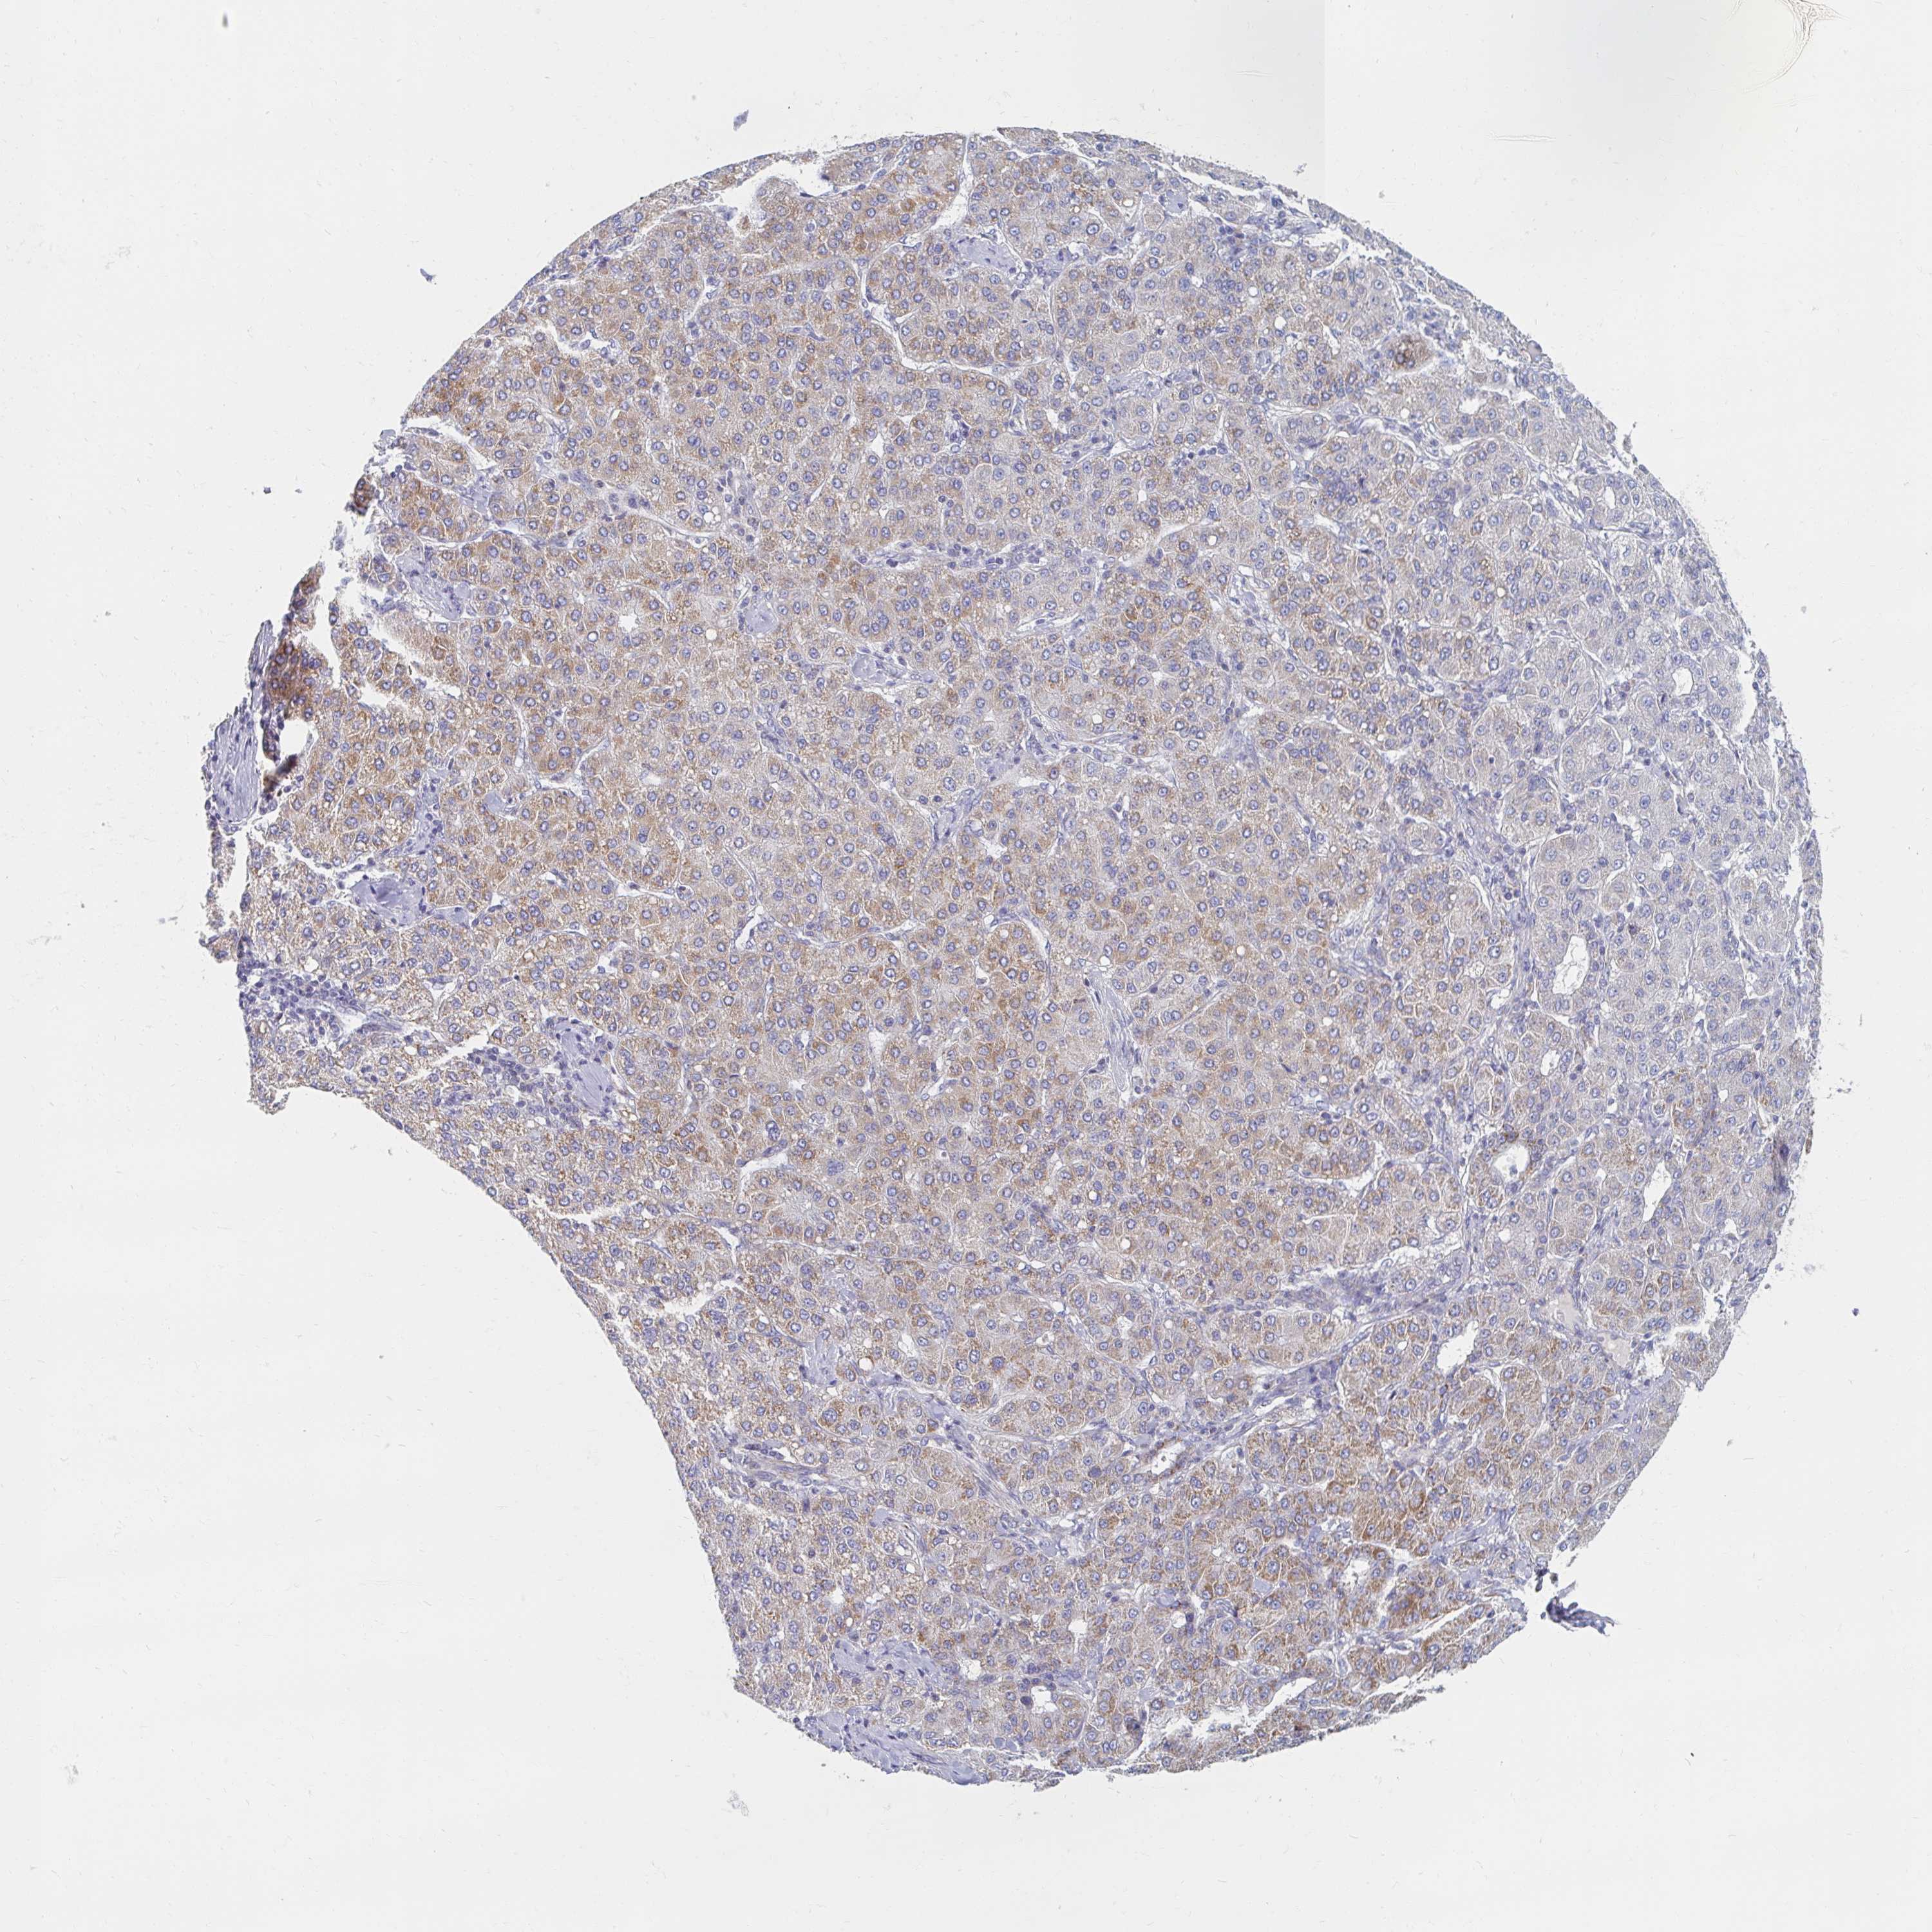

LIVER CANCER - Protein expressioni

A mouse-over function shows sample information and annotation data. Click on an image to view it in a full screen mode. Samples can be filtered based on level of antibody staining by selecting one or several of the following categories: high, medium, low and not detected. The assay and annotation is described here.

Note that samples used for immunohistochemistry by the Human Protein Atlas do not correspond to samples in the TCGA dataset.

Antibody stainingi

Antibody staining in the annotated cell types in the current human tissue is reported as not detected, low, medium, or high, based on conventional immunohistochemistry profiling in selected tissues. This score is based on the combination of the staining intensity and fraction of stained cells.

Each image is clickable and will lead to virtual microscopy that enables deeper exploration of all samples and also displays staining intensity scores, fraction scores and subcellular localization as well as patient and tissue information for each sample.

Antibody HPA049850

Antibody HPA053524

Antibody CAB009187

Staining

High

Medium

Low

Not detected

Intensity

Strong

Moderate

Weak

Negative

Quantity

>75%

75%-25%

<25%

None

Location

Nuclear

Cytoplasmic/membranous

Cytoplasmic/membranous,nuclear

Carcinoma, Hepatocellular, NOS

Cholangiocarcinoma